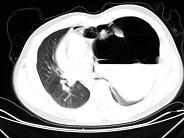

女,6岁,胸闷,咳嗽,胸部CT如图,最可能的诊断为 ( )A.畸胎瘤B.右侧液气胸C.右肺肺大疱D.右侧脓胸E.支气管囊肿并感染